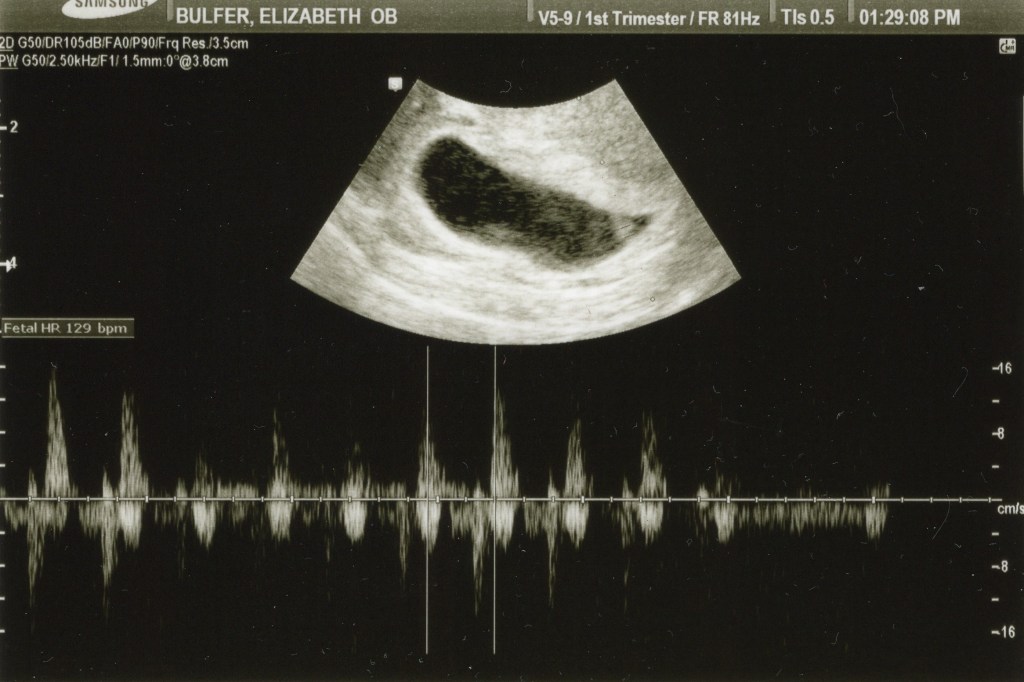

The first trimester of an infertility pregnancy is primarily handled by the infertility clinic. Some clinics graduate you at 8 weeks, while others follow you until 12 weeks. We graduated from our fertility clinic at 10 weeks, right before New Years. My clinic does the first ultrasound at week 6 to check on viability. At that point, the baby is just a little stick, potentially with a heartbeat, hanging out in a small sack called the “yolk sack.” The yolk sack is a sack of nutrition that feeds the baby until the placenta is fully developed between weeks 10 and 12. We went for our six week scan, and were lucky enough to even hear the heartbeat for a moment! At six weeks, you may not even get a chance to see the heartbeat, let alone hear it! We felt very lucky!

At the ultrasound on Monday, our little baby was growing appropriately, still had a strong heartbeat, and we saw the source of the problem. I had a fairly large subchorionic hematoma (SCH), it can also be called a subchorionic hemorrhage. An SCH is a pocket of blood that forms between the wall of the uterus and the amniotic sack, in about 1% of pregnancies. Yes, just one percent. However, for some unknown reason, they are far more common in fertility treatment pregnancies (especially IVF pregnancies) than in the general public. This article from What to Expect does a fantastic job explaining them.

The SCH in my uterus was less than 50% of the size of the amniotic sack, which my doctor said pointed to fantastic outcomes. She said a bleed that was less than 50% the size of the sack was very unlikely to cause issues with the pregnancy. While that was comforting, it’s still terrifying to bleed during pregnancy. Every single time I went to the restroom, there would be spotting either in my underwear or on the toilet paper. Thankfully, I never bled heavily again after that initial event.

Since an SCH can cause complications, I was put on pelvic rest, which is different than bed rest, stayed on a higher dose of progesterone, and got ultrasounds every other week to check on the baby. Pelvic rest means “don’t do anything that can stress the pelvis,” which means nothing inserted into the vagina, no orgasms, no lifting anything that causes you to strain (even slightly), and only low impact and non-bouncy exercises (no running, etc). I stayed on pelvic rest until week 13, progesterone continued until I was at week 12, and I had a scan every other week until week 12.